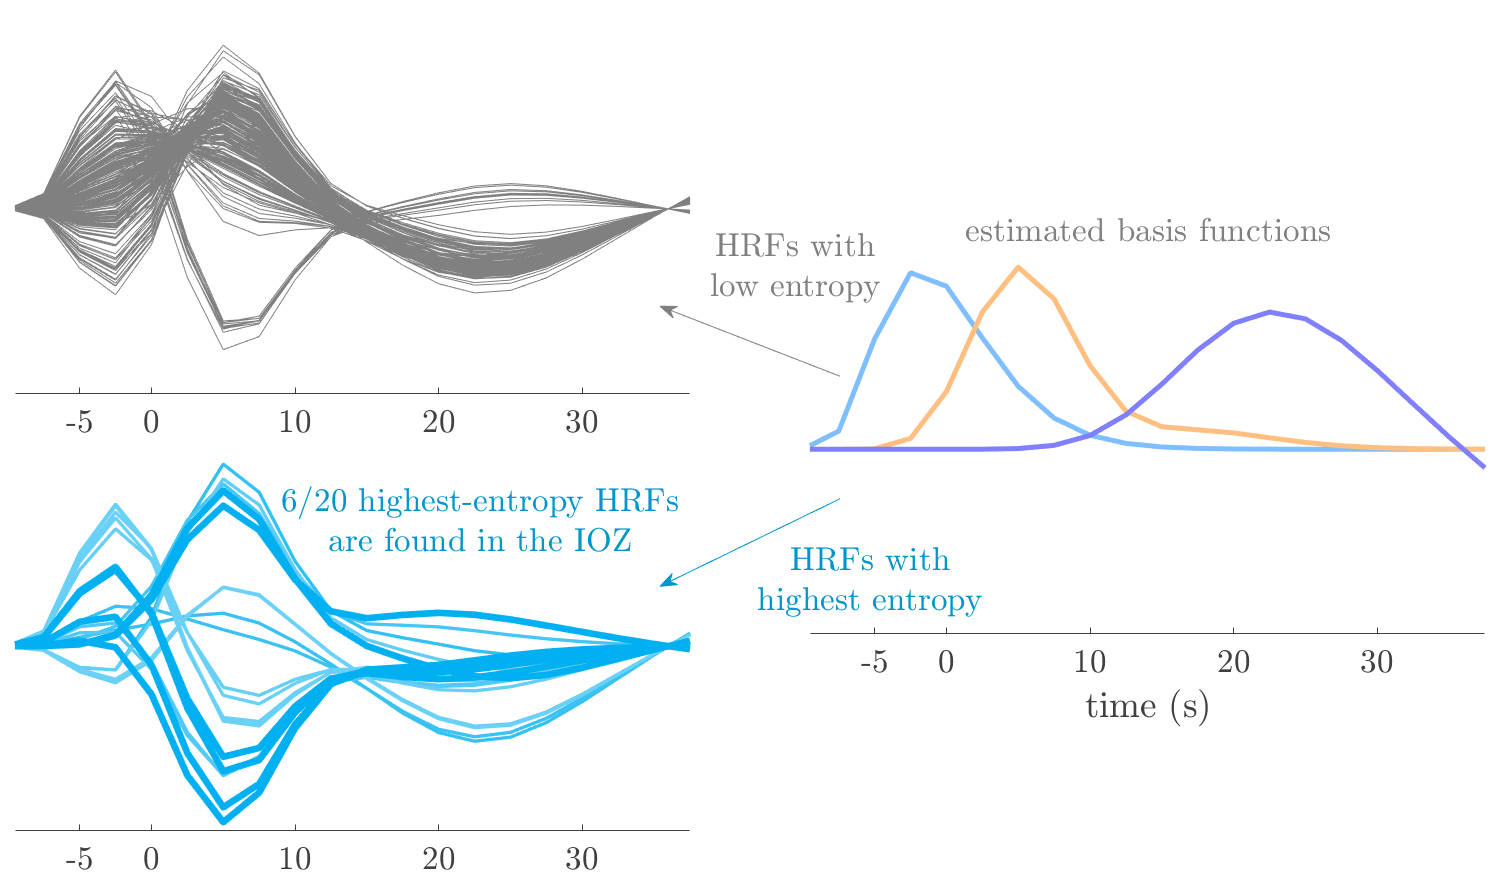

Patient 1

We analyze the solution with sources. Figure 1 shows the EEG signatures and HRF waveforms. One of the sources is highly correlated to the MWF reference (in grey), which was already known from Table B.3. This IED-related source had a typical low-frequency spectrum, which is expected for the typical spike-and-wave interictal discharges. The topography is relatively diffuse, although the highest amplitudes are mostly in the left hemisphere. This is in accordance with the lateralization of ictal onset zone (left temporal lobe, cfr. Table 1). There are some noteworthy observations to be made about some of the other components. The fourth has an unusually sharp spectrum, is mainly localized on two nonadjacent center electrodes, and is sustained for a single period of many seconds Hence, this component likely captured an artifact (of yet unknown origin), although we spotted no large-amplitude changes in the EEG itself. Similarly, the third source is only present at one frontal electrode, and exists in a frequency range above 20 Hz. It might represent a muscle artifact, e.g., due to frowning or twitching of some muscles in the forehead. The HRFs of all ROIs are shown in Figure 1(b). Two of the basis functions seem to have converged to a very similar waveform, which is an unfortunate possibility if two initial HRFs are too close to the same local optimum in their respective parameters. This reduces the expressive power of the basis set, which is clearly visible, since many ROIs have a nearly identical HRF. One of the twenty ROIs with the highest-entropy HRF overlapped the IOZ, although clearly this HRF (bold line) is not among the most dissimilar waveforms for this patient. This is also visible in Figure 2: both the HRF entropy and extremity maps show a small overlap with the delineated IOZ. Despite the good correspondence in the EEG domain, no significant (de)activation of the IED-component is found inside the IOZ.

Patient 2

We analyze the solution with sources, and show the results in Figure 3 and 4. As for patient 1, we found a source which is strongly correlated to the MWF envelope, and which had a mostly low-frequency behavior characteristic for spikes. The topography is mostly uninformative, and does not clearly correspond to the patient’s clinical data. The third source is mostly present at both sides of the head, is very sparsely active in time, and has a high-frequency content: this is most likely an artifact due to the neck muscles. Again, there is one of the highest-entropy HRFs which belongs to a ROI in the IOZ. Now, the waveform is clearly resolved from the other HRFs, through the strong initial dip (before 0 seconds). Such a dip is sometimes observed in HRFs, but its underlying physiological mechanism is not yet fully understood. It is possible that this dip reflects altered vascular autoregulation near the IOZ (cfr. the explanation in the Section 1 of the main text), or a rapid depletion in oxygen due to IED generation (before the IED becomes visible on the EEG). Figure 4 furthermore shows that the IED-related component is significantly active in parts of the IOZ, and deactive in others. As mentioned earlier, this deactivation may or may not be due to errors in sign correction. Interestingly, the ROI with the high alteration in neurovascular coupling is distinct from both the activated and deactivated ROIs.

Patient 4

We analyzed the solution with sources, and show the results in Figure 5 and 6. There is one source which is mostly correlated to the reference (but not extremely, see also Table B.3). This source had a right-temporal focus, conform the diagnosis in Table 1. The second source illustrates the phenomenon of an erroneous sign exchange between the spatial and spectral profiles. Also one of the HRFs has a negative polarity, which is a failure of the sign correction procedure (in this case, because there is exceptionally no positive overshoot). However, the HRF variability metrics are still interpretable, and indeed two ROIs among the ones with the highest-entropy HRFs overlap with the IOZ. The IED component is significantly active in a tiny portion of the IOZ (cfr. Figure 6). The second source is significantly active in symmetrical parts of the parietal lobe. Given its ongoing fluctuation over time, we hypothesize that this source captures a resting state network (RSN).

Patient 5

We analyze the solution with sources, and show the results in Figure 7 and 8. There is a clear IED-related component, with a very high correlation to the MWF reference, a typical spectrum, and an anterior-temporal focus, which corresponds very well to the patient’s diagnosis (cfr. Table 1). The fifth source seems present at only one channel, and has spectral harmonic at Hz and Hz. One of these peaks is reminiscent of the fourth component in patient 1. As Figure 8 shows, the HRF entropy and extremity prove to be strong biomarkers for the IOZ in this case, and also the significant IED activation and deactivation allow correct localization. In Figure 7, it is clear that some HRFs may still have the wrong sign, which means that the interpretation of ‘active’ and ‘deactivated’ is flipped in those ROIs. Hence, regions of significant deactivation are in fact significantly activated. The fourth source had a significant overlap with the auditory RSN, and its spectrum reveals activity in the band.

Patient 6

We analyze the solution with sources, and show the results in Figure 9 and 10. One source is strongly correlated to the MWF, while the other source is likely an artifact, given its very sparse temporal profile. Both sources coincide at one high-amplitude peak, by which we infer that this is probably an artifactual period in the signal. Indeed, when inspecting the original EEG signals, we found high-frequency muscle artifacts at these times. This source also had no significant activation in its spatial map, which corroborates its non-neuronal origin. The IED-related source had a broader spectrum than most other cases, and an uninformative topography. None of the ROIs with high-entropy HRFs is located in the IOZ. The pseudo t-map provides correct localization of the IOZ, however.

Patient 7

We analyze the solution with sources, and show the results in Figure 11 and 12. We found a clear IED-related component, with a characteristic spectrum and a topography which is backed up by the patient’s diagnosis (left anterior-temporal IOZ). The fourth source has a very similar topography and spectrum to the fifth source in patient 5. One HRF inside the IOZ had a high-entropy, and is distinguishable from the others by its very sluggish waveform, i.e., it is smeared out in time, with no sharp over- or undershoot. Also the pseudo t-map provided an accurate localization of the IOZ. Notably, in this patient, the extremity metric misses the deviating HRF in the IOZ (while the entropy metric picks it up). The second source overlapped with the frontal part of the default mode network (DMN), and is active in the and low bands.

Patient 8

We analyze the solution with sources, and show the results in Figure 13 and 14. We found two components which had correlated time courses. At the time of the peaks, we found higher-amplitude events in the EEG with dubious origin, hence they may or may not be artifacts. One of both components is more strongly correlated to the MWF, and its activation is concordant with the IOZ. The second component shows high overlap with the sensorimotor network. For this patient, none of the IOZ’s ROIs had extreme values of either HRF metric.

Patient 9

We analyze the solution with sources, and show the results in Figure 15 and 16. In this patient, there is only a moderate correlation of a component with the MWF reference time course. This component’s topography (left occipital) agrees with the clinical description, however. The HRF extremity (and not the entropy) is high in a small part of the IOZ. Both the significant IED activation and deactivation allow correct localization as well. The second source seemingly captured high-frequency oscillatory activity in the sensorimotor network, similar to the previous patient.

Patient 11

We analyze the solution with sources, and show the results in Figure 17 and 18. The IED-related source had a high correlation with the MWF reference, but an odd bimodal spectrum. Its EEG topography is very consistent with the clinical description. Both HRF extremity and entropy are useful biomarkers for the IOZ. The IED activation and deactivation maps each had a very small overlap with the IOZ. The second source is temporally sparse and captures high-frequency EEG variations, which we identified as muscle artifacts.

Patient 12

We analyze the solution with sources, and show the results in Figure 19 and 20. Again we observe an IED-related source and a seemingly artifactual source with a spectral peak near 34 Hz. Many of the high-entropy HRFs are highly noncausal, and are associated to ROIs inside the IOZ. Hence, with both HRF metrics, the highest-scoring ROIs provides good localization of the HRF. While there are no significantly active ROIs in the IOZ, there are several significantly deactivated ROIs, which may indicate that the sign standardization was not done flawlessly (cfr. also some of the negative-peaking HRFs for patient 10). Surprisingly, the second source had one significantly active ROI, which overlaps with the IOZ, but which did not match its EEG topography. Hence, the nature of this source remains ambiguous.